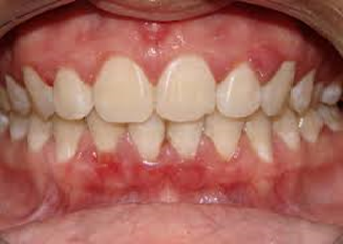

Na parte superior destes dentes vemos claramente uma Gengivite instalada. A gengiva fica, vermelha, lisa devido ao edema. As papilas ficam mais vermelhas e aumentam de volume e quando tocadas pelo fio dental sangram com facilidade.